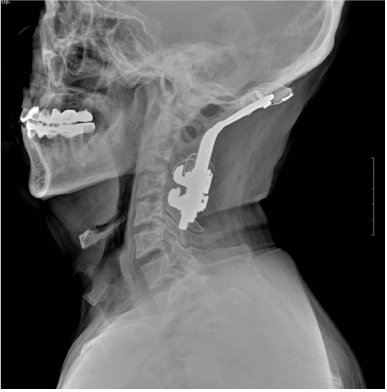

A 55-year-old man was scheduled to get a L4-5 decompression surgery due to spinal stenosis. He received occipitocervical fusion because of traffic accident in 1999 and so his occipitocervical joint was almost immobilized and his mouth opening was limited to moderate degree. And he had cleft palate of 3*5 cm and his nasal opening also showed abnormality (Figure 1). In the radiograph, his tongue base was displaced posteroinferiorly, thus covering the epiglottis, which narrowed the oropharyngeal space (Figure 2).

Figure 2. Radiograph of the side of the cervical vertebral portion. Immobilized occipitocervical junction and tongue base are overridden on the upper side of the hyoid bone.